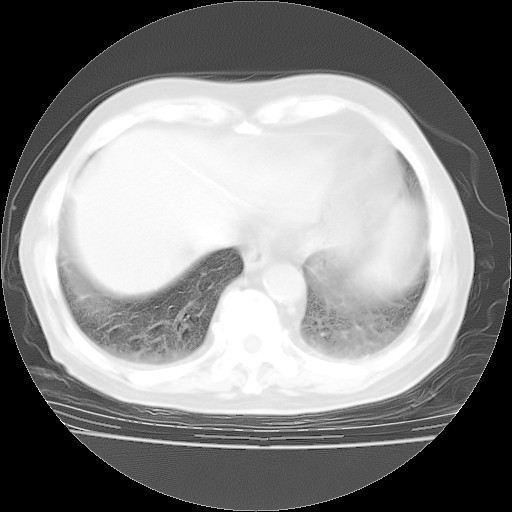

4月28日肺部CT——再次出现类似去年5月9日——透光度降低,“间质性”改变。

个人阅读4.14日肺部CT平扫:纵隔窗无异常,但肺窗示:双下肺内、后基底段有片絮状侵润影,部位以后基底段为著,以间质改变为主,呈急性肺泡炎征像,和首次住院影像学有相似之处。仅是个人读片,明日请相关专家再读片哈。其它建议同上。

1、108#的是4月14日的胸部CT(发此贴时还没看着28日的CT)。14日的胸部CT其实已经出现改变(如108#所述),个人认为28日的胸部CT除纵膈窗疑似有双侧胸膜增厚或少量胸积液(可行胸部B超明确)外,与4月14日对照病变有所加重;2、已经给予“异烟肼、利福平、乙胺丁醇”抗痨治疗?如果是,甲强龙80mg可缓慢减量;如果环磷酰胺已停用,暂不使用;3、中性粒细胞92%,明显升高,目前体温情况?注意合并细菌感染可能,使用左氧氟沙星情况下,是否联用B-内酰胺类抗菌药物?另外是查免疫全套非风湿全套。